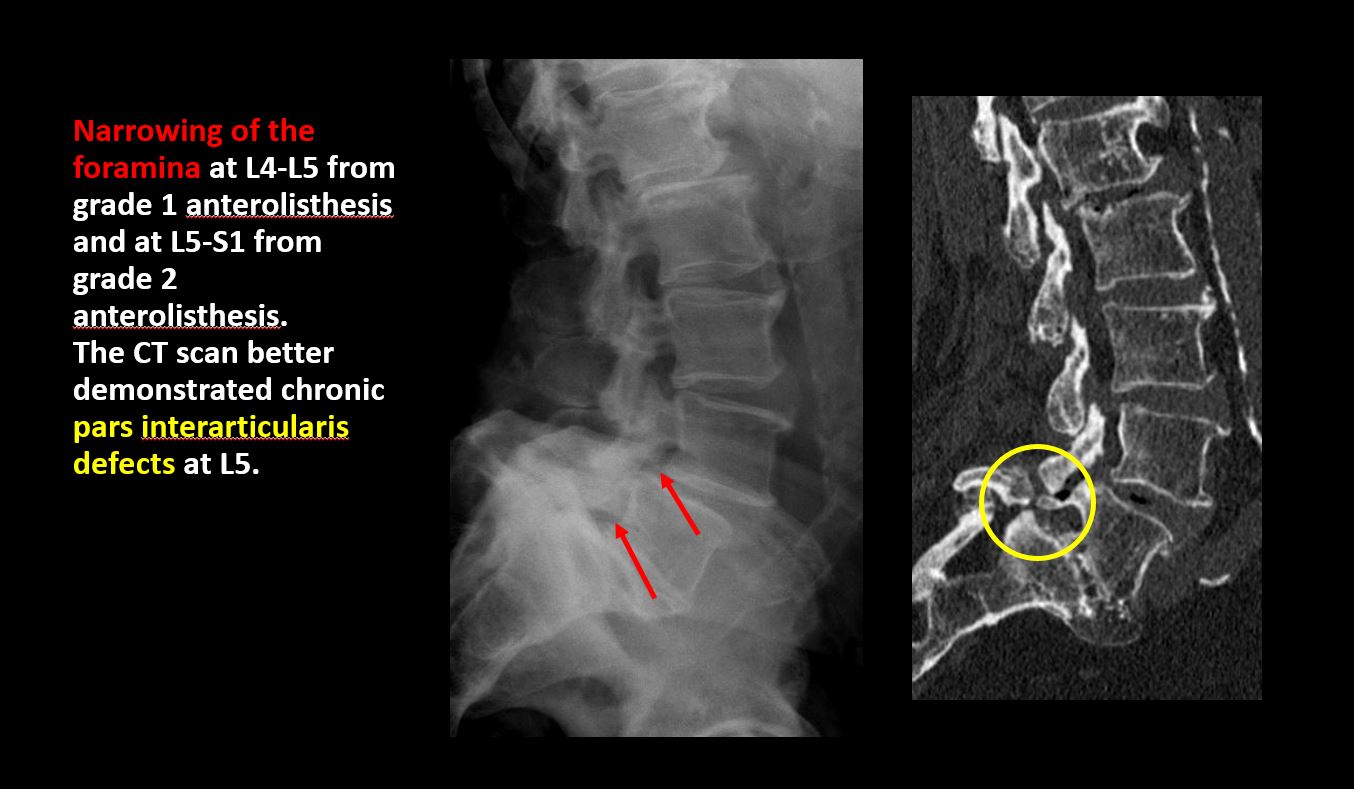

Section 1 Submit Findings CB1239 Findings Technique The thoracolumbar junction and/or the lumbosacral junction is/are not entirely included on the exam. Yes No The exam is over or under penetrated. Yes No The exam is limited by overlying structures, bones or soft tissues, patient positioning, support devices, or motion. Yes No Prevertebral and paravertebral soft tissues The prevertebral or paravertebral soft tissues are abnormal. Yes No Spinal alignment The vertebral bodies are abnormally aligned. Yes No The anterior and posterior vertebral body lines are abnormal or interrupted. Yes No The visualized spinous processes are malaligned or distracted on the AP and/or lateral view(s). Yes No There is reversal or straightening of the normal lordosis or scoliosis of the lumbar spine. Yes No Vertebral bodies, posterior elements and included sacral segments There are more or less than the expected 5 non rib-bearing vertebral bodies. Yes No There is a transitional motion segment at the lumbosacral junction (sacralization of L5 or lumbarization of S1). Yes No There is a fracture or distraction of a vertebral body, transverse or spinous process, or other posterior element. Yes No There is anterior wedging and/or compression of a vertebral body or end plate. Yes No There is an end plate avulsion or other fracture. Yes No There is displacement of a fracture fragment into the soft tissues or spinal canal. Yes No There is lucency or defect of the pars interarticularis from spondylolysis. Yes No There is an abnormality of a pedicle or lamina on the frontal or lateral view. Yes No There is a fracture, erosion, sclerosis, lytic, or blastic lesion of a pedicle or lamina. Yes No There is evidence of a lytic or sclerotic lesion, or disruption of the trabecular pattern of a vertebral body, end plate, or sacrum. Yes No There is a fracture or interruption of the arcuate lines of the sacrum. Yes No There is erosion, sclerosis, narrowing, or other abnormality of a sacral foramen or the SI joints. Yes No There is focal or diffuse abnormal mineralization of the lumbosacral spine. Yes No Disc spaces and facet joints There is distraction or focal widening of a disc space. Yes No There is disc space narrowing with or without erosive or sclerotic changes of the end plates or subchondral bone other than from degenerative change. Yes No There is anterior or posterior spondylolisthesis, subluxation, or rotational abnormality at a disc space. Yes No There is widening, rotational abnormality, or displacement of facets at any motion segment. Yes No There is facet joint narrowing or sclerosis other than from degenerative change. Yes No There is narrowing or encroachment of a neural foramen other than from degenerative change. Yes No There are degenerative changes present that might explain the patient’s symptoms. Yes No Additional soft tissues and bones (lower thorax, abdomen, and pelvis) There is abnormal bowel or bowel gas pattern. Yes No There are gallstones, vascular, renal, pelvic, or other soft tissue calcifications present. Yes No There is free intraperitoneal or retroperitoneal air or other abnormal air in the included chest, abdomen, or pelvis. Yes No The included thoracic spine, ribs, and remainder of the bony pelvis are abnormal. Yes No There is abnormality of the lower chest and/or diaphragm. Yes No There is a foreign body or there are post surgical changes of the bones or soft tissues of the included lower thorax, abdomen, and pelvis. Yes No There is an abnormality or complication of post surgical hardware/device. Yes No N/A There are support lines or tubes in an abnormal position. Yes No Other findings There are other existing conditions that might be contributing to symptoms which can or should be further evaluated non-emergently. Yes No